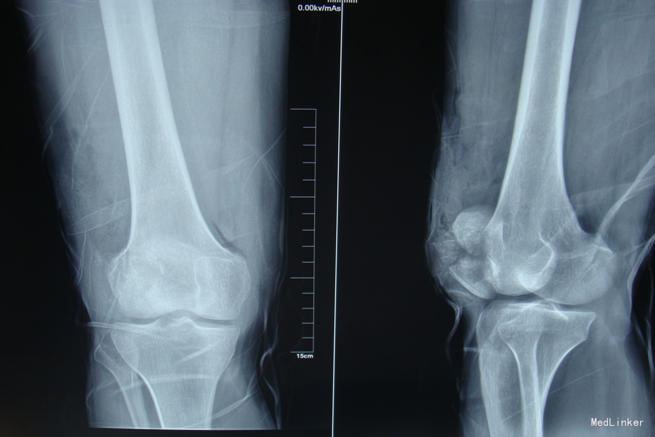

主诉:右膝关节疼痛活动受限2小时。现病史:2小时前马车坠落,摔伤致左膝关节疼痛、流血、活动受限,患者于当地医院行左膝X线检查,提示:左髌骨骨折,包扎,为进一步处理。患者现无意识障碍,无视物不清,无头晕、头痛,无恶心、呕吐,无胸闷及呼吸困难,无腹胀、腹痛。现平素饮食睡眠良好,二便如常。发病近期体重无明显下降。

专科查体::左膝见一长约10cm的开放口,压痛(+)。未触及骨擦感及异常活动,未闻及骨擦音,患肢无明显 麻木,左下肢血运良好,余肢体查体未见明显异常

中医诊断:右髌骨骨折额(气滞血瘀)西医诊断:右髌骨骨折 治疗:切开复位张力带内固定术。中医辨证论治:根据骨伤科三期辨证理论,早期因瘀血停滞影响骨痂生长,故以活血化瘀,消肿止痛为 主,应用桃红四物汤;中后期补益肝肾,补气养血,应用愈骨胶囊等药物应用。现患者属于骨折早期, 可运用桃红四物汤加减对症治疗,方药如下: 桃仁10g 红花10g 当归12g 川芎12g 赤芍12g 穿山甲6g 柴胡12g 黄芩10g 香附12g 延胡索15g 续断15g 生地12g 甘草6g 3剂 用法:每日一剂,水煎服400ml,分早晚两次温服。 中医调护:避风寒,慎起居,忌生冷,畅情志。